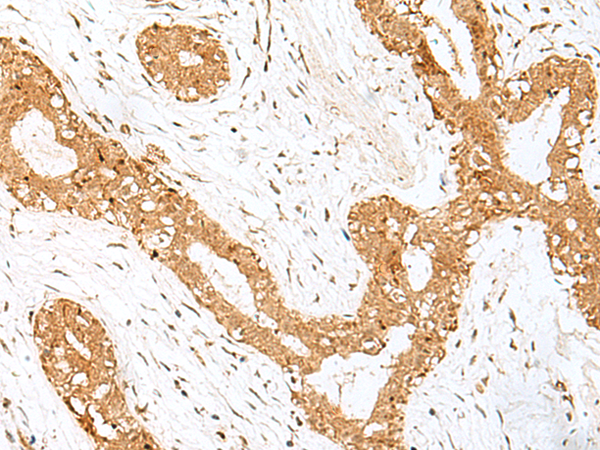

IHC positive control: |

Human thyroid cancer |

IHC Recommend dilution: |

40-200 |